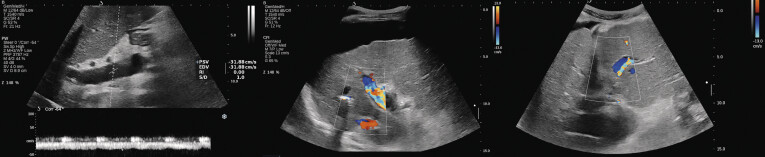

Background   Ultrasound (US) surveillance for transjugular intrahepatic portosystemic shunt (TIPS) dysfunction has yet to be standardized, as clear-cut criteria have not been conventionally defined. This study evaluated the role of US-based parameters in detecting hemodynamic TIPS dysfunction (HD). Methods   We included consecutive patients treated with TIPS. All patients were scheduled within the first six weeks after the procedure for TIPS revision, comprised of a Doppler US exam and invasive hemodynamic reassessment. Clinical TIPS dysfunction (CD) was defined as symptom recurrence, while HD was defined by a portal pressure gradient (PPG)≥12 mmHg. The predictive capabilities of Doppler US for predicting TIPS dysfunction were tested against the hemodynamic gold standard. Results   86 patients were included. Secondary prophylaxis of variceal bleeding was the main indication for TIPS in 72 patients (83.7%), while 27 (31.4%) had refractory ascites. HD occurred in 37 cases (43%), of which 25 patients (67.5%) had no CD. Patients with HD had a significantly lower portal vein velocity (PVV): 35 (20-45) cm/s vs. 40.5 (35-50) cm/s, p=0.02. Compared to the immediate post-TIPS assessment, the patients without HD had a ΔPVV of 6.08±19.8 cm/s vs. a decrease of - 8.2±20.2 cm/s in HD (p=0.04). Using a cut-off value of 40.5 cm/s, PVV had an AUROC of 0.705 for predicting HD, while the addition of ΔPVV (cut-off 9.5 cm/s) improved the AUROC to 0.78. Conclusion   Despite adequate symptom control, a considerable percentage of patients have a post-TIPS PPG≥12 mmHg. The dynamic assessment of PVV and its temporal dynamics can reliably predict TIPS dysfunction.

Abstract Image